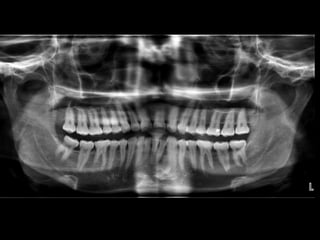

 Orthopantomography